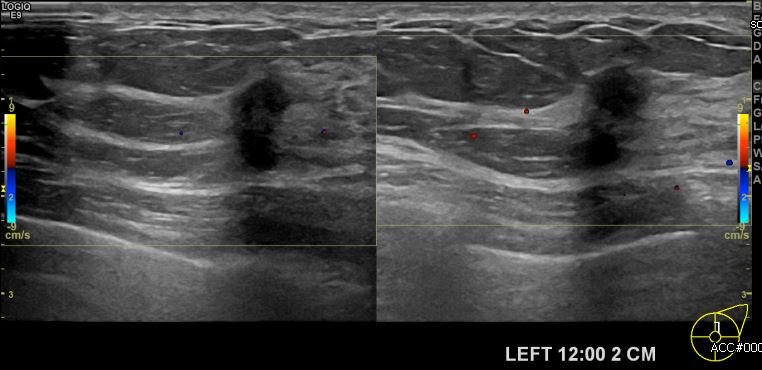

상기환자 건강검진상 이상 소견으로 내원하신 40대 여성분으로 좌측 12시 방향에서 2cm

떨어진 거리의 의심스러운 멍울 조직검사 시행하여 좌측 침윤성 유관암 진단 되었습니다.